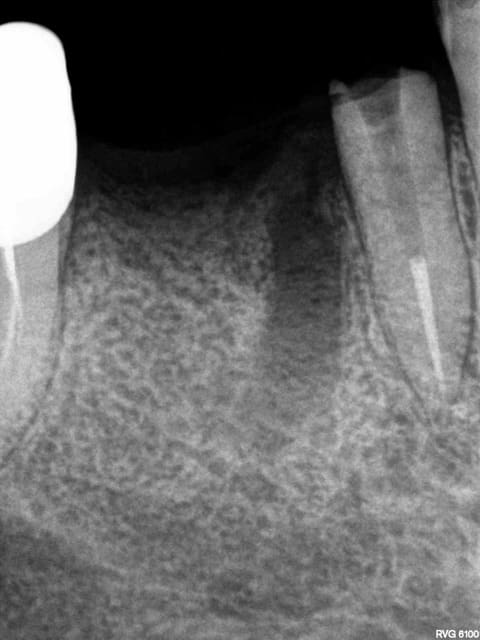

Exemple endo 45 taille empreinte. ( mac spaden) 35 mn.

Radio cone en place, cone scellé, mac spaden, logement tenon.

Manque de la place sur les trays zirc, ca serait bien d'en avoir des plus grands-)))))